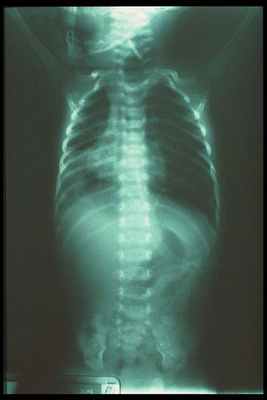

На обследовании выполняются рентгеновские снимки грудной клетки и брюшной полости, предварительно в пищевод устанавливают рентген-контрастный зонд. Исследование проводится в прямой проекции в вертикальном положении ребёнка. Оценивают уровень стояния зонда (свёрнутый зонд в слепом верхнем сегменте); газонаполнение желудка и кишечника (при наличии трахео-пищеводного свища между нижним сегментом и трахеей будет определяться воздух в брюшной полости, при отсутствии воздуха в желудке и кишечнике исключается наличие нижнего трахеопищеводного свища).

Далее обязательно проводится рентгенологическое обследование для подтверждения диагноза. На обзорном снимке грудной и брюшной полостей начало зонда определяется в слепом конце пищевода, далее наличие газа в желудочно-кишечном тракте позволяет дифференцировать свищевые формы атрезии пищевода. Отсутствие газа в желудке при обзорной рентгенографии чаще всего связано с отсутствием сочетания атрезии пищевода со свищем в трахею.